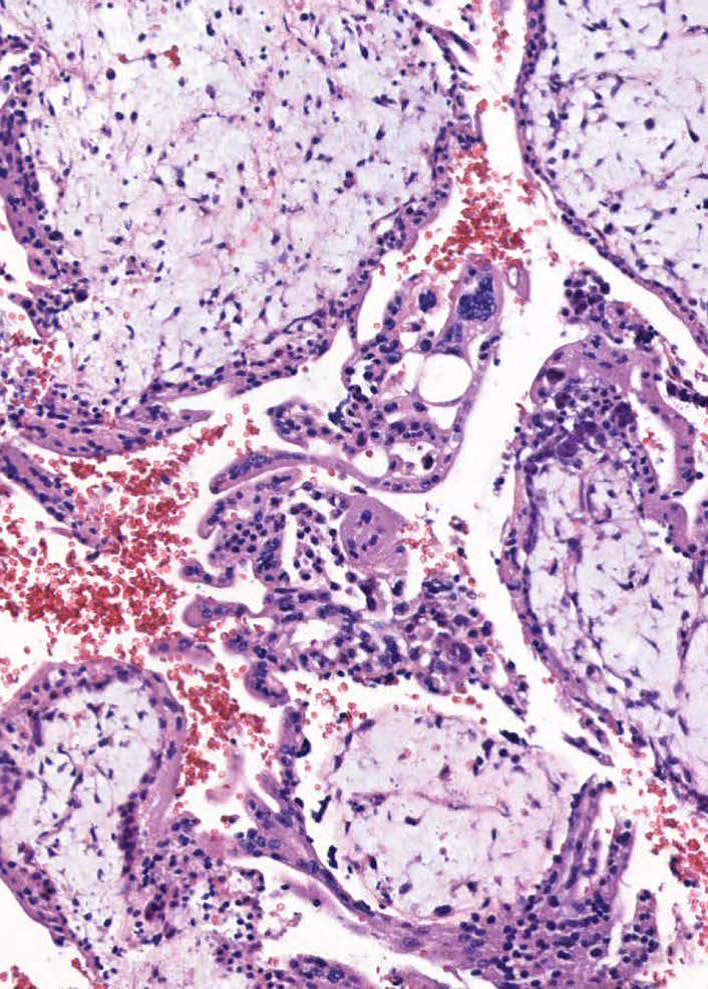

- Gestational trophoblastic neoplasia (GTN) is defined by a plateaued, rising, or prolonged elevated β-hCG value after molar evacuation; histologic diagnosis of choriocarcinoma, invasive mole, placental site trophoblastic tumor, or epithelioid trophoblastic tumor; or identification of metastasis after molar pregnancy evacuation.